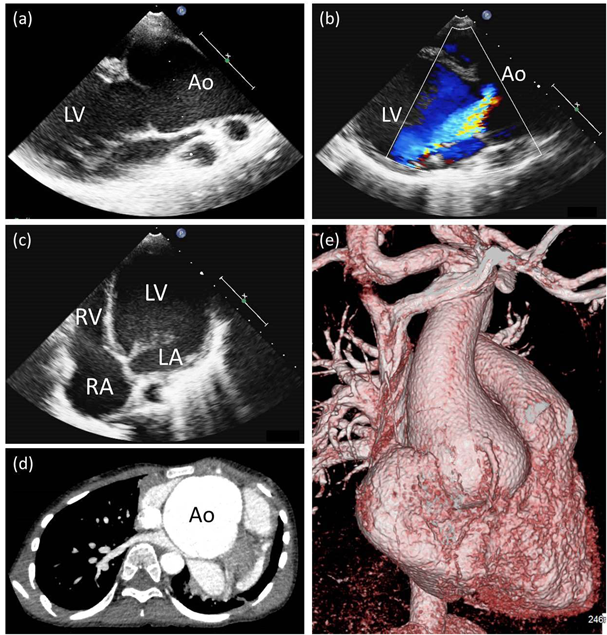

FBN1遺伝子第29番エクソンのスプライシング異常による早期発症型Marfan症候群の一例Early-onset Marfan Syndrome Caused by a Splicing Mutation of FBN1 Exon 29: A Case Report